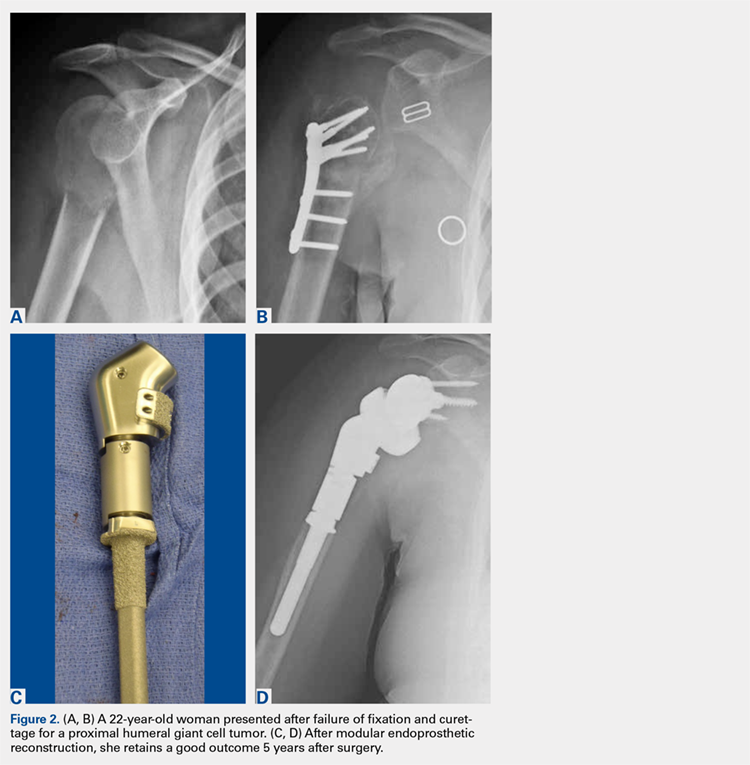

Modular endoprostheses have been evaluated as a method for improving bone fixation and restoring soft-tissue tension, while avoiding the complications associated with traditional endoprostheses or allografts (Figures 2A-2D). These systems allow precise adjustments of length using different trial lengths intraoperatively to obtain proper stability and deltoid tension. Of the 12 patients in a 2 center study, 11 had cementless components inserted using a press-fit technique (unpublished data, J. Feldman). At a minimum 2-year follow-up, the patients had an average improvement in forward elevation from 78° to 97°. Excluding 2 patients with loss of the deltoid tuberosity, the forward elevation averaged 109°. There were significant improvements in internal rotation (from 18° to 38°), as well as in the scores of Quick Disabilities of the Arm, Shoulder and Hand (DASH), forward elevation strength, ASES, and VAS pain. However, the overall complication rate was 41%. Therefore, despite these promising early results, longer-term studies are needed.